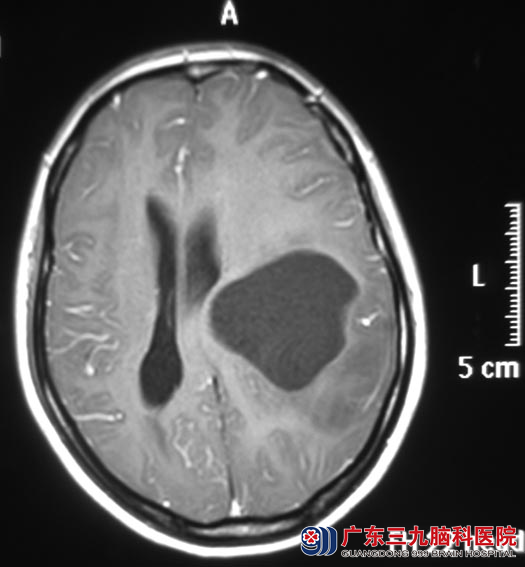

CT检查提示:左侧额顶叶囊实性占位;广东三九脑科医院头颅MR检查提示:左侧额顶叶示一较大的囊实性占位性病变影,病变实性部分边界不清,囊性不稳边界清楚,大小约为67.3mm×65.2mm×64.8mm,脑干明显受压,左侧环池变窄。

▲手术前